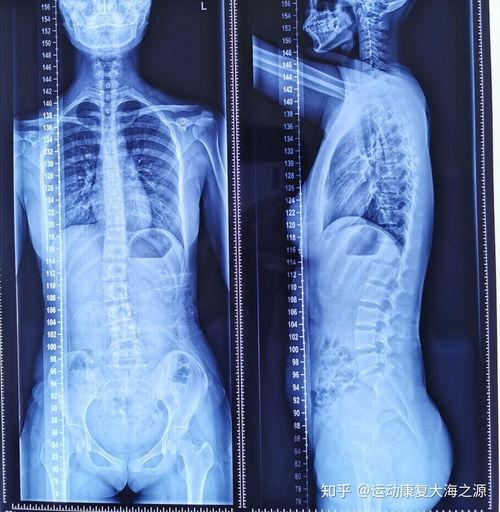

首先,让我们来了解一下什么是脊柱侧弯。脊柱侧弯,顾名思义,就是脊柱在X光片上呈现出的侧弯状态。这种状况可能会影响一个人的外观、姿势,甚至呼吸。据统计,全球约有3%的人患有脊柱侧弯,其中女性患者多于男性。